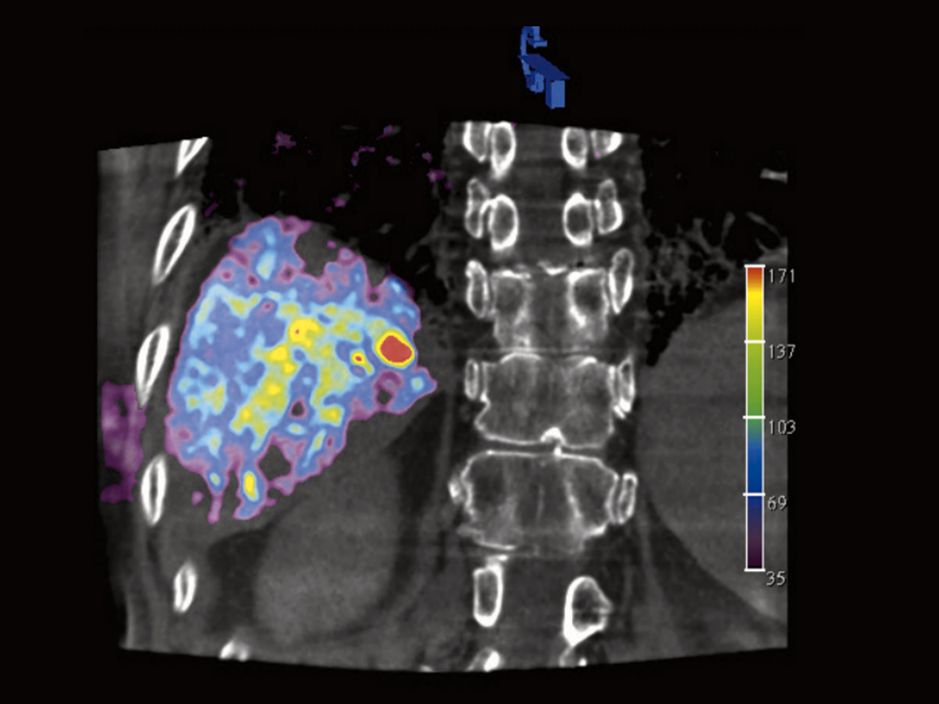

Courtesy: Prof. Gerd Groezinger, Interventional Radiology, University Hospital Tuebingen, Germany

syngo DynaPBV Body blood volume map only